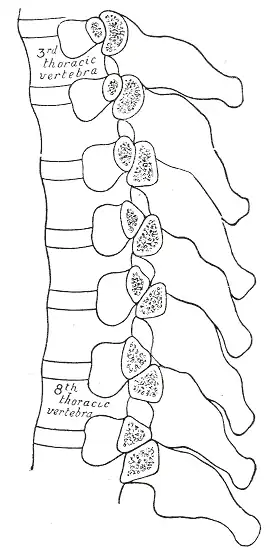

Lateral surface of the thoracic vertebrae. Right half of the thoracic skeleton is not shown.

Lateral surface of the thoracic vertebrae. Right half of the thoracic skeleton is not shown. -